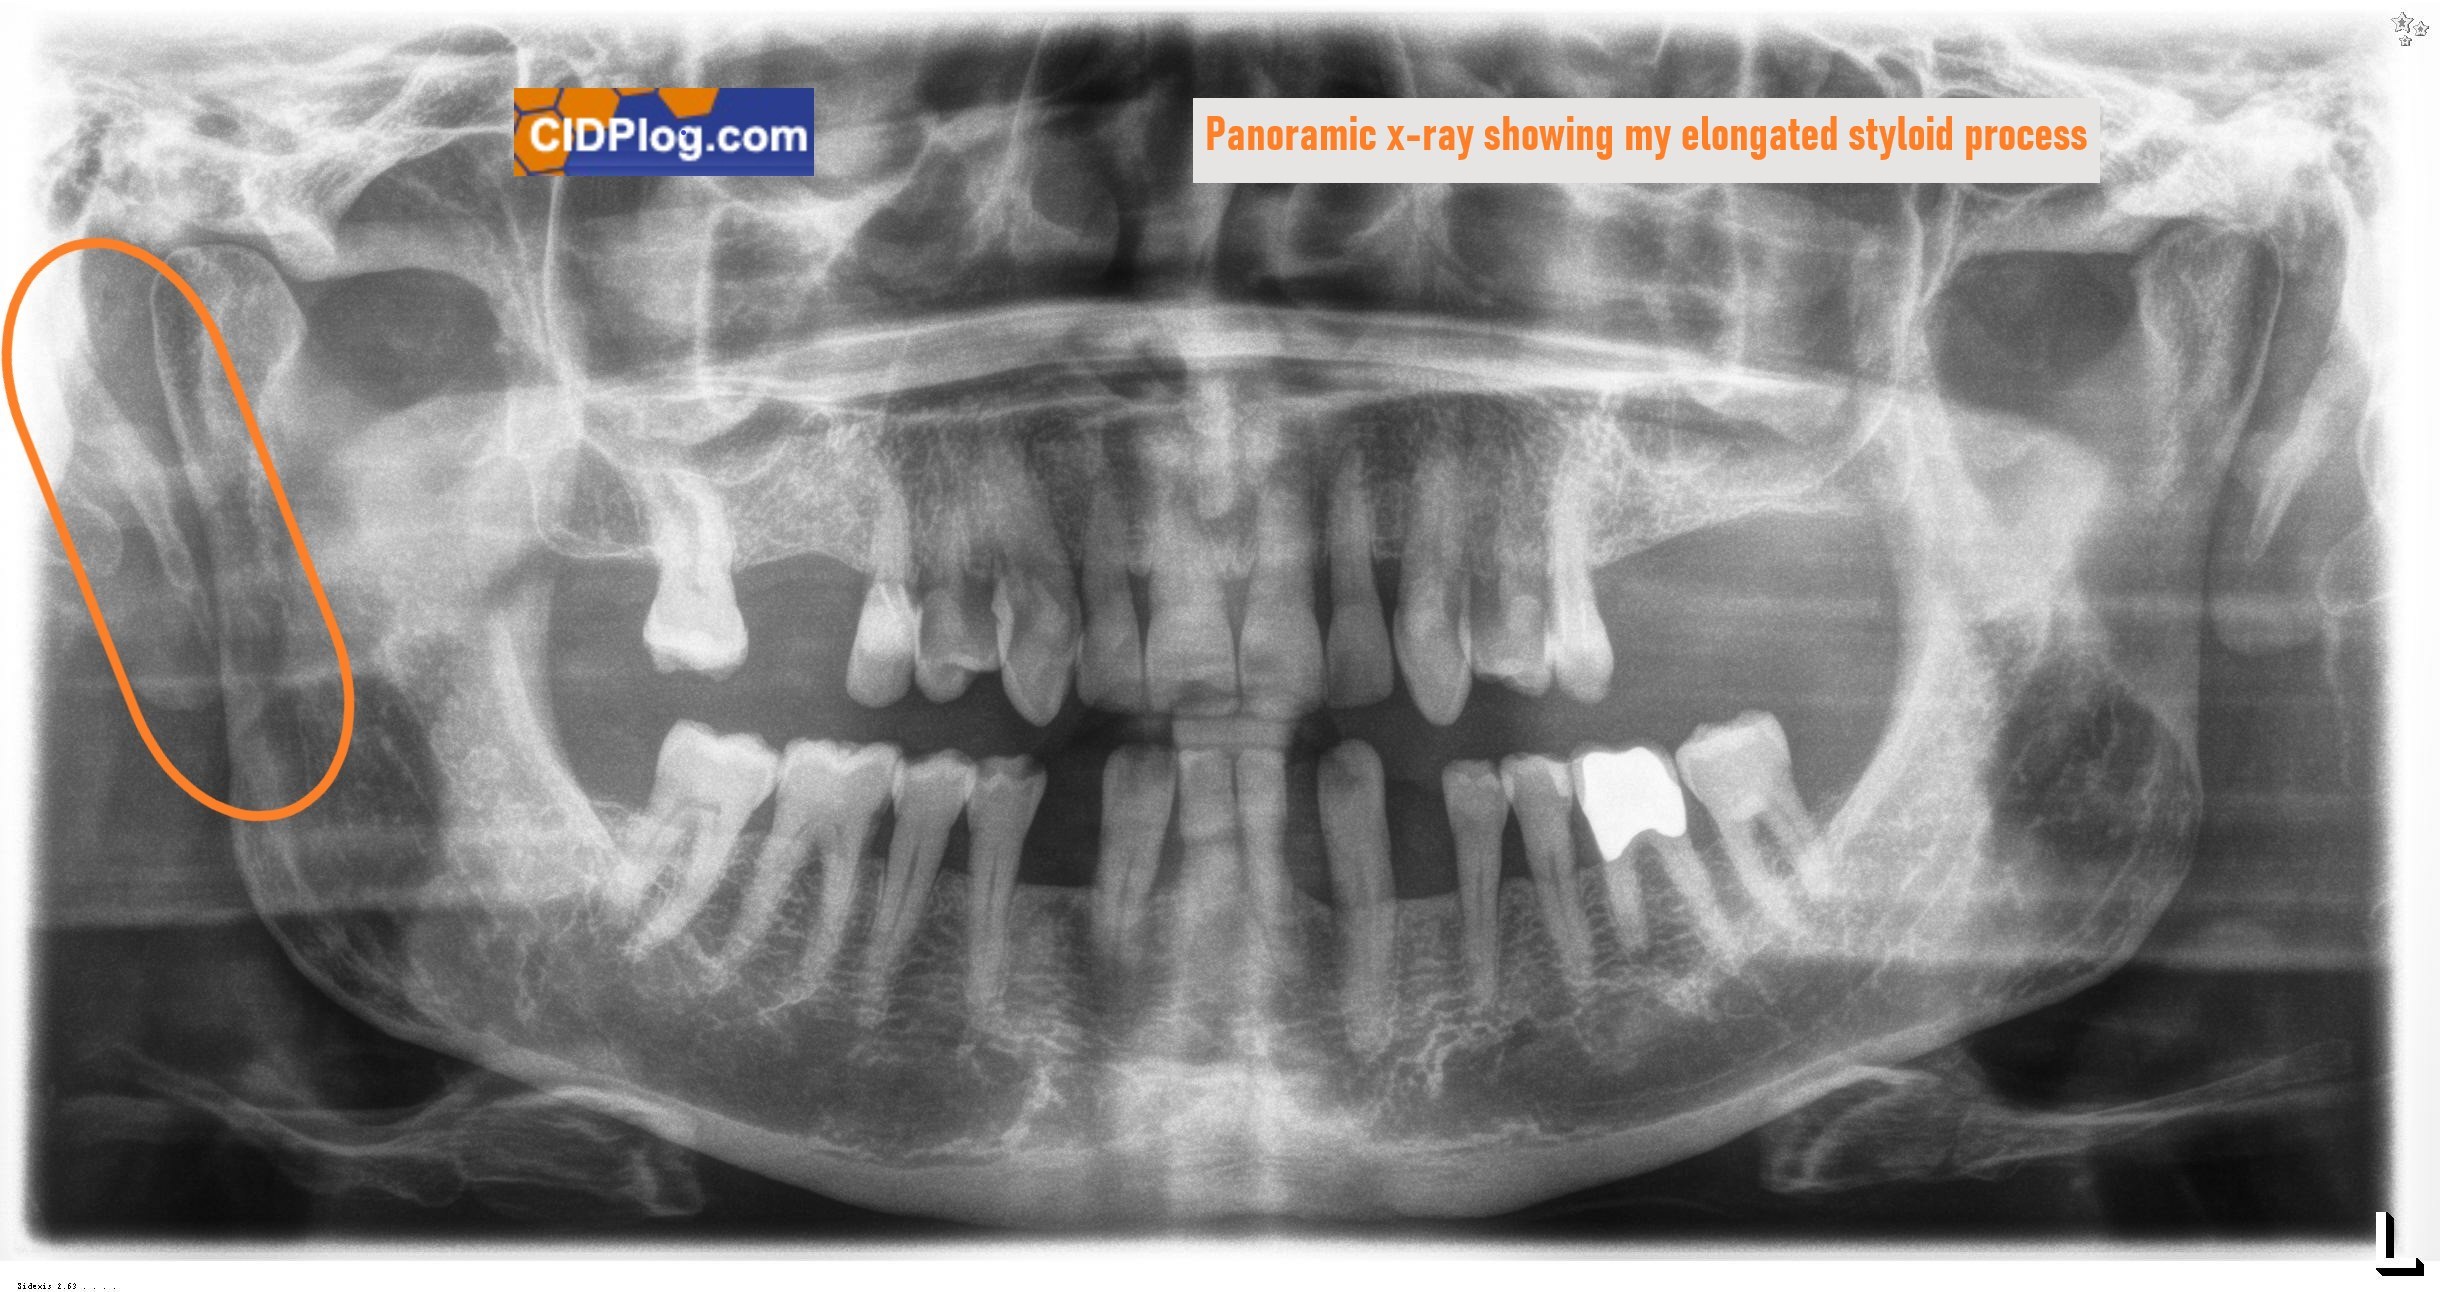

» July 16, 2024 Eagle Syndrome Diagnosis: a potential breakthrough on eye / facial pain as I have a diagnosis of "Eagle Syndrome", believe it or not after referral by my dentist!. I received the diagnosis less than a month after I consulted a (Canadian) ear, nose and throat surgeon who said I was in perfect condition! I had previously seen more than a handful of doctors and came up with a highly questionable diagnosis, a blank, or denial that anything was wrong. Eagle Syndrome caused by an elongated styloid process and/or calcified stylohyoid ligaments, could explain pretty much all my eye/ head/ face issues as it effects the vagus nerve and carotid arteries. Autonomic dysfunction is a feature of Eagle’s Syndrome, See panoramic x-ray showing my elongated styloid process. The vagus is the longest cranial nerve and comprises both sensory and motor fibers. he vagus nerve functions contribute to the autonomic nervous system, which consists of the parasympathetic and sympathetic. There are four forms of Eagle Syndrome: